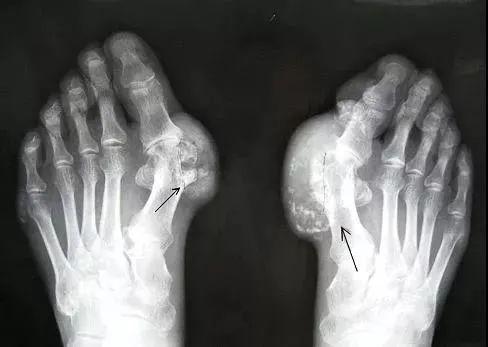

什么是痛风?

所谓痛风

是由尿酸盐沉积导致的

一种晶体相关性关节病

痛风的病因是「高尿酸血症」

就好比水里的盐浓度太高了

慢慢被析出来就形成“尿酸结晶”导致痛风

痛风自然病程一般有4个阶段

痛风石与慢性痛风性关节炎等

痛风性关节炎急性发病期

受累关节会发热、变得暗红、肿胀

感觉有刀割或咬噬样疼痛

如果治疗不当

会迁延不愈或转移到其他关节